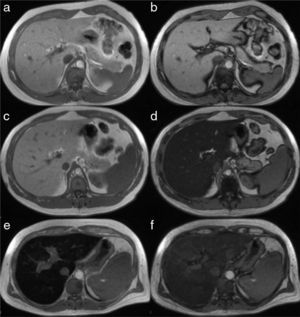

The simplest technique is the visual analysis of the image of the liver obtained in the dual echo T1-weighted sequence that makes up part of all MR liver protocols. It provides a pair of good quality anatomic images of the liver, “weighted to T1” and in 2 distinct acquisition phases: one “in-phase” (IP) and the other “out-of-phase” (OP) that enable the visual and qualitative detection of fat. In the normal patient, the liver parenchyma has the same signal in both the in-phase and out-of-phase images (Figure 5a and 5b). In patients with steatosis, signal decay in the “out-of-phase” images is produced, making the image of the liver turn darker, the greater the quantity of triglycerides (Figure 5c and d), enabling the fat fraction to be calculated, as described further ahead.

Image of the liver in the in-phase (left column) and out-of-phase (right column) T1 sequence in 3 different patients. In a normal patient, the signal is similar in the a) in-phase and b) out-of-phase sequences. The images in the center are those of a patient with steatosis in whom the intensity of the parenchymal signal is normal in the “in-phase” sequence (c) and it markedly decays in the “out-of-phase” sequence, where it acquires a tone of black due to the greater fat content (d). The bottom row corresponds to a patient with hemochromatosis. The signal decays in the “in-phase” sequence (e), due to the increase in iron saturation, compared with the “out-of-phase” sequence (f).

The dual echo T1 sequence can make a rapid qualitative appreciation of the increase in the hepatic iron content due to the fact that in this sequence the decay presents in the IP image (Figure 5e and f), in contrast to what occurs in the case of steatosis, as described above.